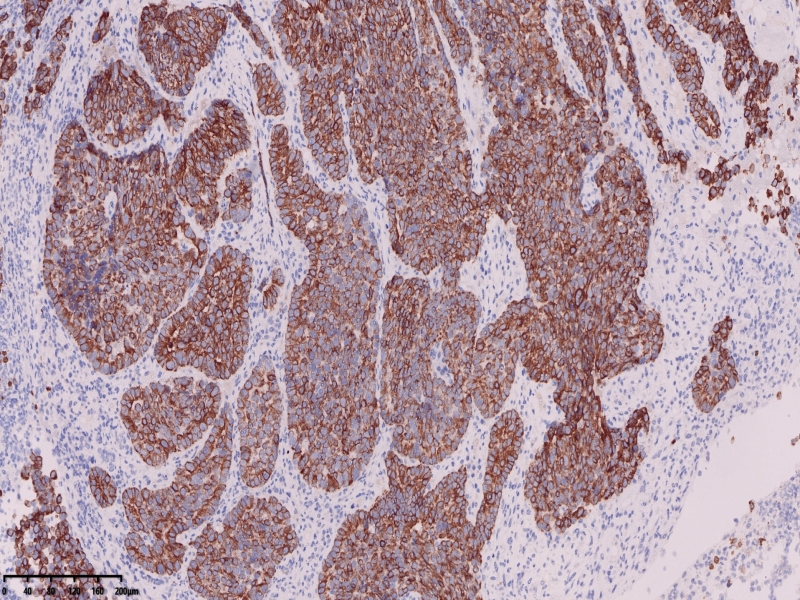

镜下所见:胃粘膜组织数块,炎症背景,其中3块固有层内可见细胞团,瘤细胞排列呈条索状迂回后呈巢状,巢的边缘瘤细胞呈栅栏状。细胞形态似柱状。

免疫组化:ki67增值指数较高约80%,CK7VillinCAM5.2、CEA+,CA19-9CDX-2部分+

KI67